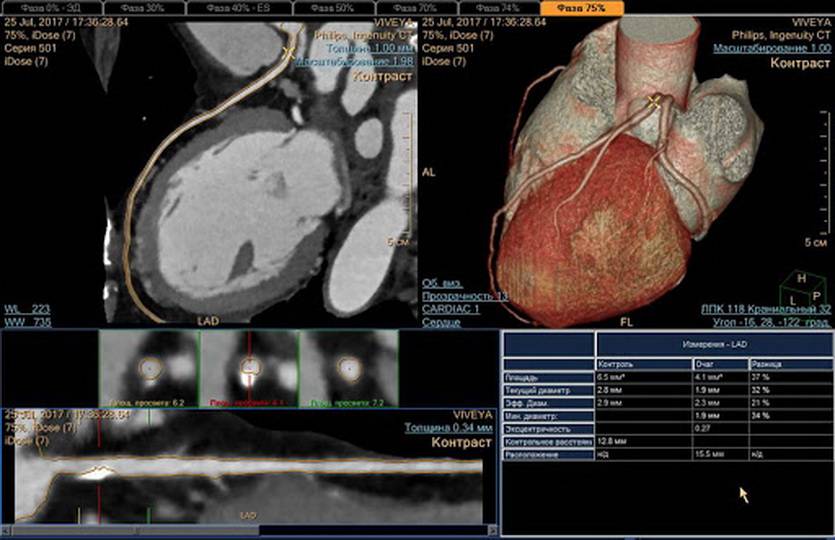

Преимущества КТ

Томография позволяет строить сложные трехмерные модели

Если аномалия на рентгене может спрятаться за чем-то другим, поглощающим рентгеновское излучение лучше (так «исчезают» за костями многие опухоли), от КТ ей не убежать: специалист может повернуть изображение нужной стороной.

Точно так же с помощью трехмерного изображения оценивают состояние сложных поверхностей, практически неидентифицируемых на рентгене. Например, не только размеры, но и форму органов со всех сторон.

Что ещё интереснее, с помощью современных аппаратов для КТ с высокой скоростью генерации пучков излучения можно получить изображение в динамике. Посмотреть не только что, но и как.

Кровеносную систему в динамике иначе не увидеть

Поэтому результаты КТ-обследования куда ближе к ультразвуковым способам исследования (УЗИ), чем к обычному рентгену, от которого они наследовали только базовый принцип работы.

Что лучше МРТ или КТ легких?

В диагностических центрах томографическое обследование легких осуществляется с помощью МРТ или КТ легких, а что из них лучше? Оба этих метода осуществляют исследование органов грудной клетки с последующей передачей информации на компьютер и ее расшифровкой. Во избежание сомнений при выборе КТ или МРТ легких и бронхов как метода исследования следует разобраться в особенностях компьютерной и магнитной томографии, и тогда станет понятно, в каких случаях показан тот или иной метод исследования, и какие противопоказания есть у сканирования органов грудной клетки с помощью компьютерной или магнитной томографии.

Приоритетным экспертным методом диагностики легких и бронхов считается компьютерная томография. Она способна точно воспроизводить детали изображения с охватом широкого спектра плотностей легочной ткани и выявлять начальные признаки морфологической перестройки при опухолевом и некротическом поражении. На первом этапе пациентам с заболеваниями легких обычно назначают выполнить рентгенографию в стандартных проекциях для исключения очаговых и инфильтративных изменений в легких. Если данные рентгеновских снимков носят тревожный характер, для уточнения диагноза, дифференциальной диагностики болезни легких и бронхов вторым шагом врач назначит сделать мультиспиральную компьютерную томографию органов грудной клетки. Она позволяет идентифицировать все мелкие повреждения в легочной ткани, которые имеют особое клиническое значение при выявлении опухолей, пневмонии, астмы, туберкулёза, хронической обструктивной болезни легких. Если данные КТ легких предполагают наличие злокачественного поражения, в качестве дополнительного метода могут назначить пройти МРТ легких с контрастом, чтобы оценить степень инвазии опухоли в ткани средостения и лимфатические узлы.

Компьютерный томограф получает изображения за счет способности рентгеновских лучей проходить сквозь ткани различной плотности с разной скоростью. В легких содержится много воздуха, потому рентгеновские лучи в них не задерживаются, что дает хорошую тканевую контрастность, если в легких и бронха есть новообразования. Поскольку КТ аппарат делать множественные снимки с большой скоростью, он менее чувствителен к артефактам движения. Все это делает КТ более точными информативным методом диагностики легочных заболеваний по сравнению с магнитно-резонансной томографией.